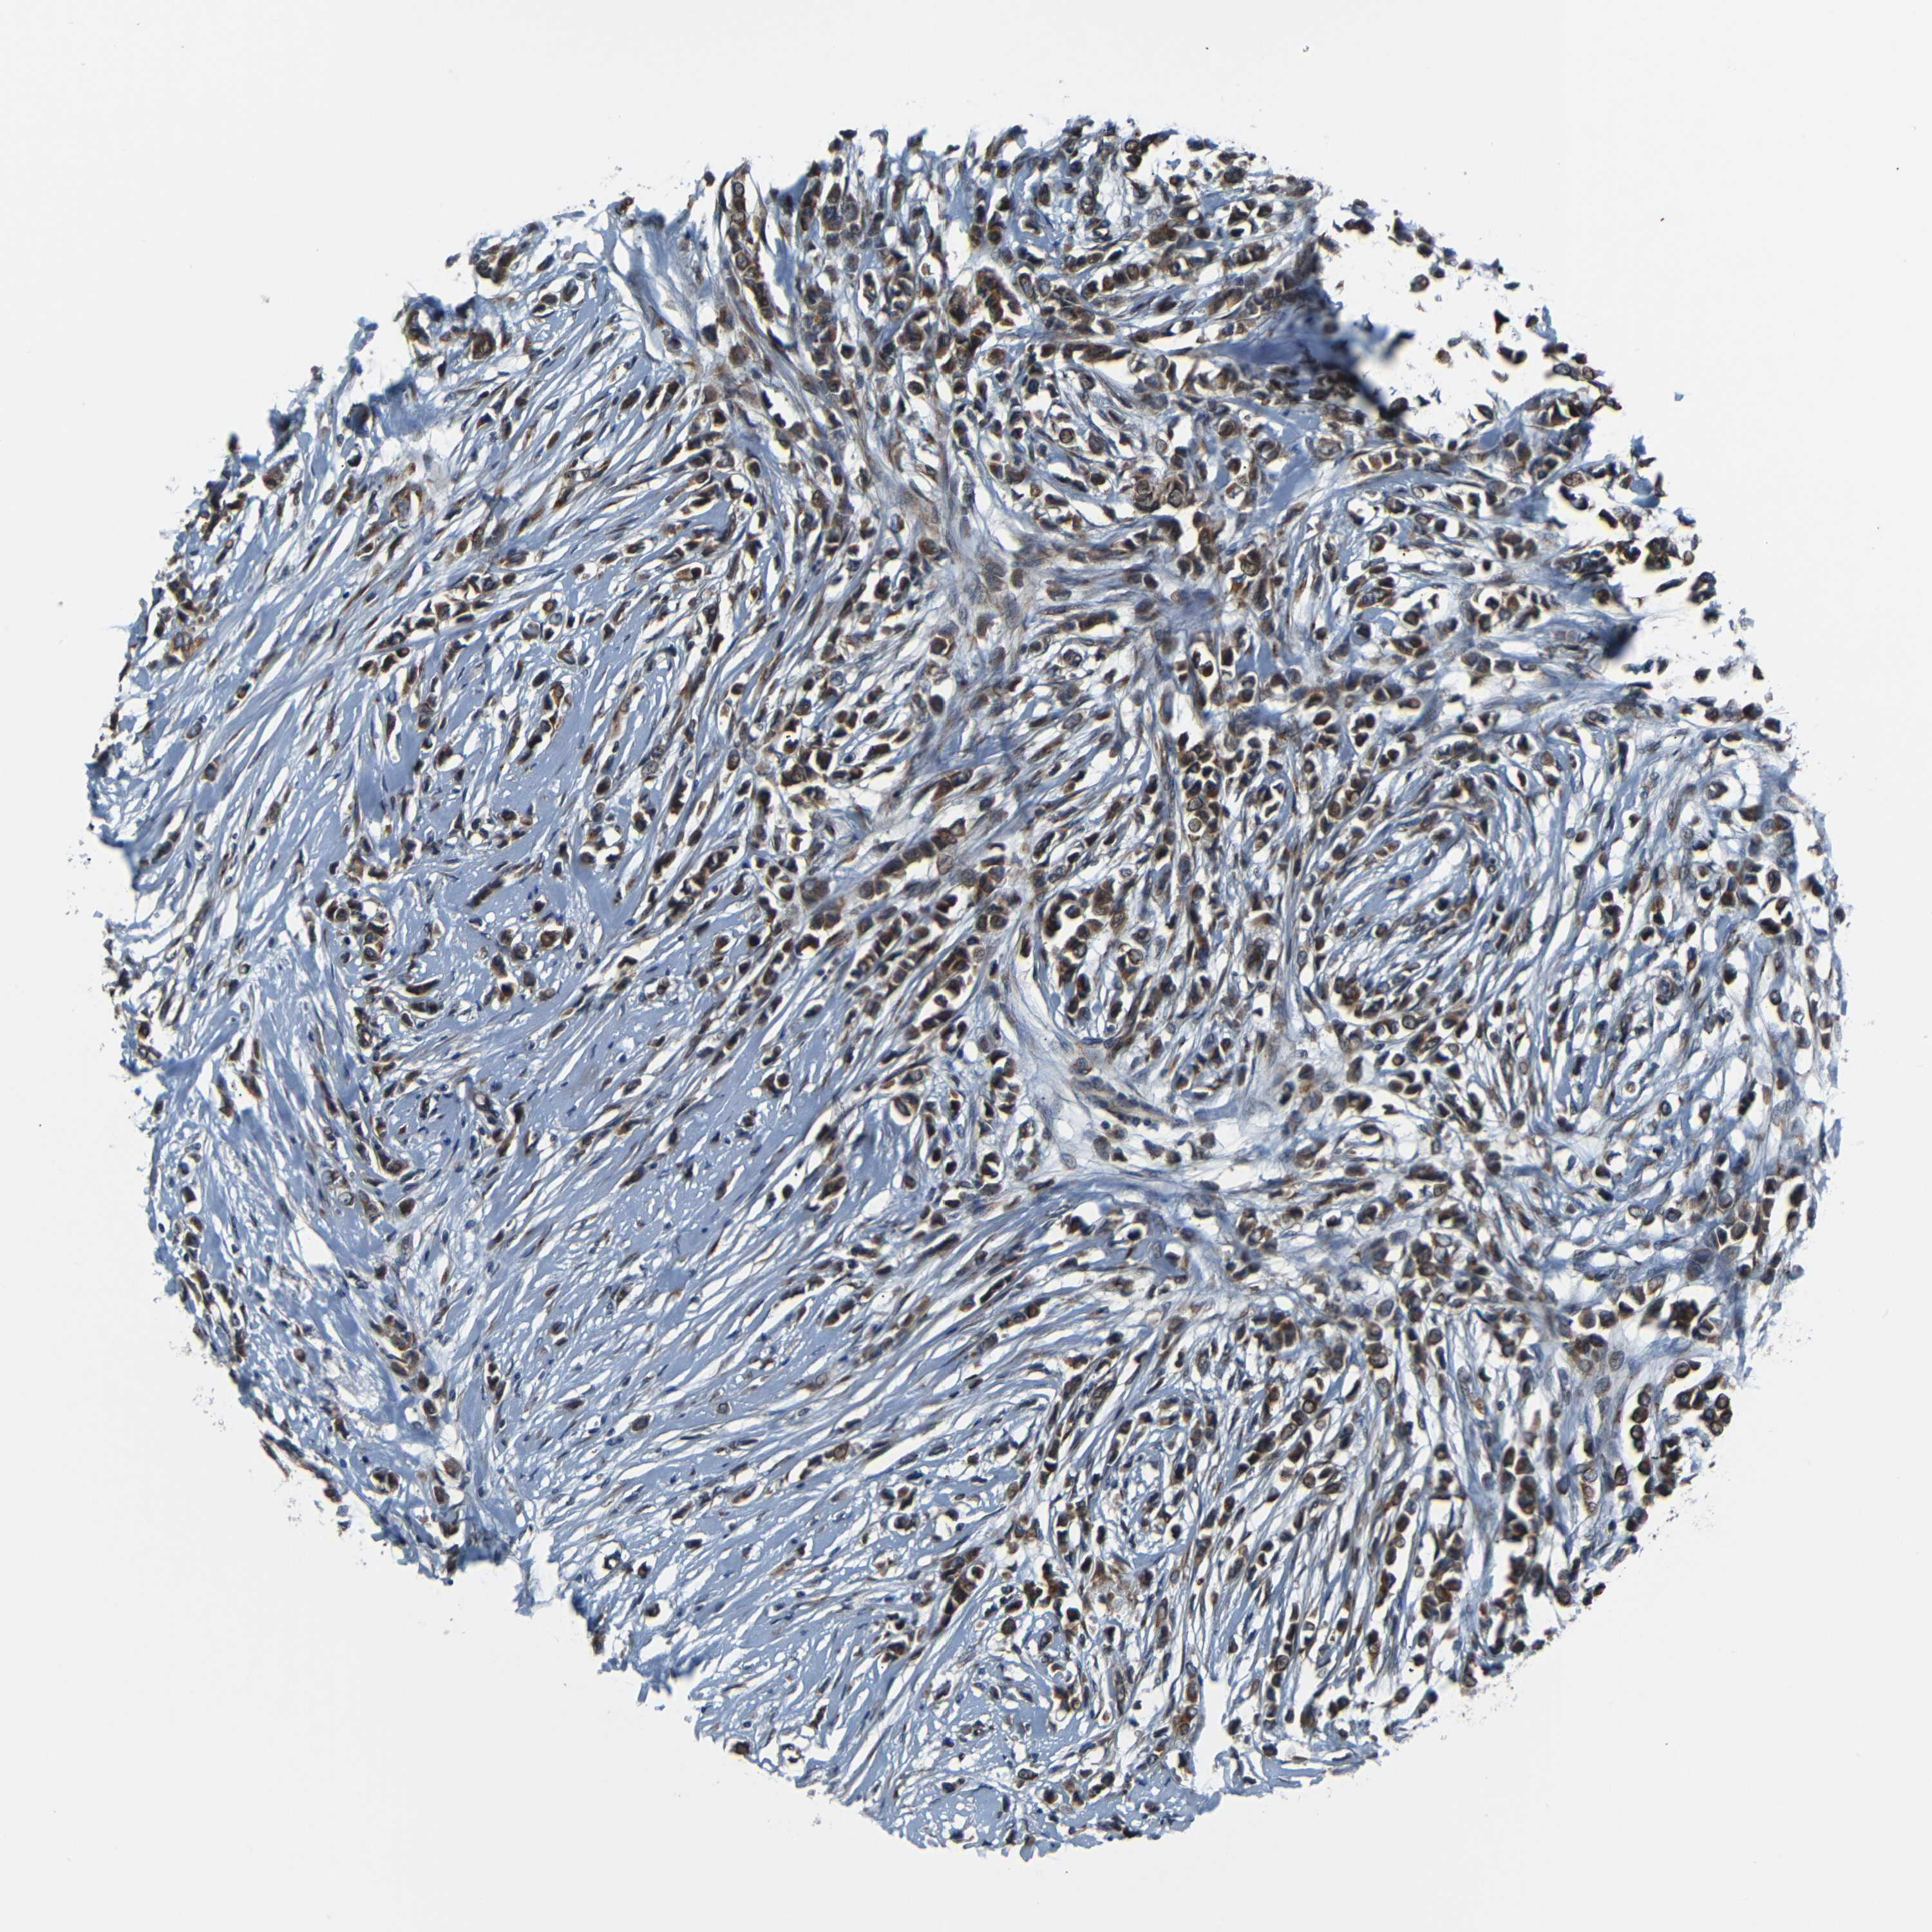

BRCA TCGA BRCA VALIDATION PROTEIN EXPRESSION

ANTIBODIES

AND

VALIDATION